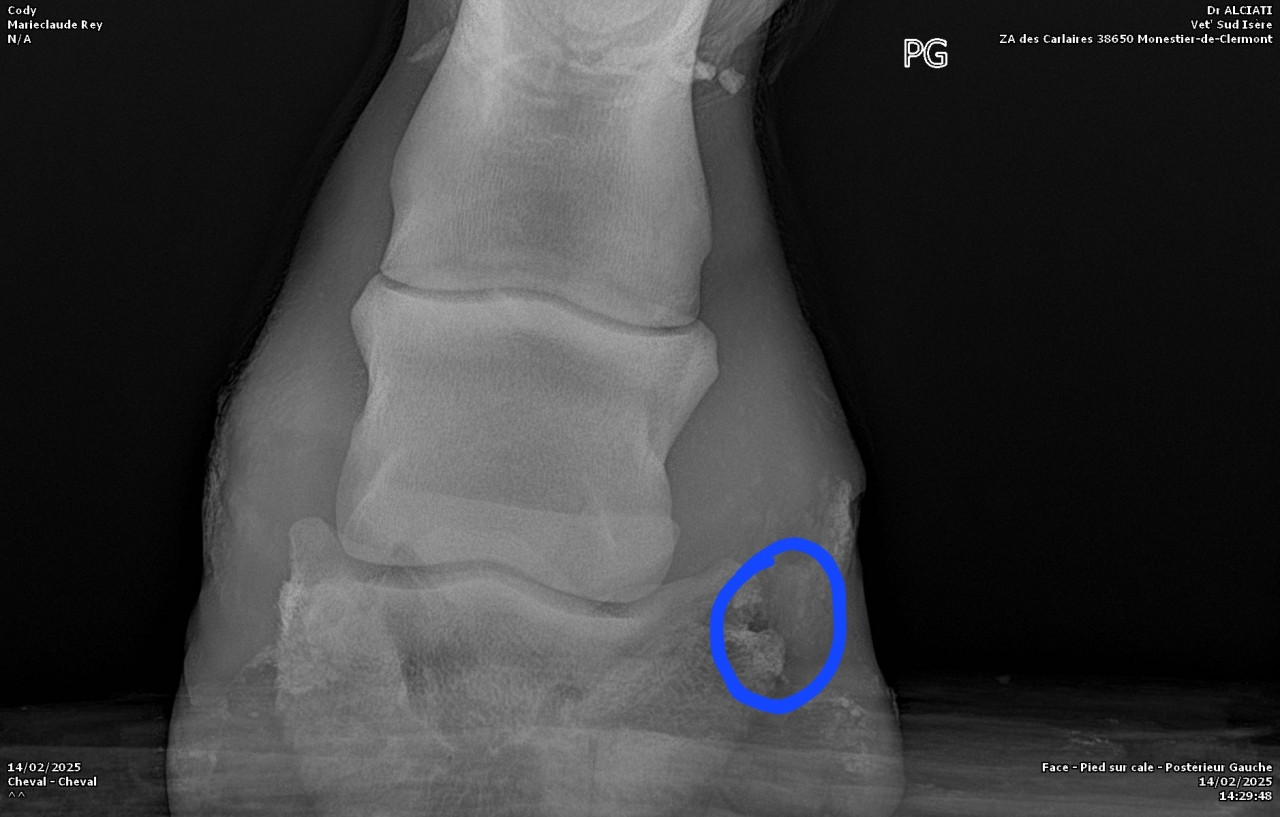

| Dire merci | Voici les radios :![]() ![]() |

DéconnectéDire merci | Personne n'a répondu à tes photos de radios parce que je suppose que comme moi, on ne se sent pas compétent pour l'interpréter. Qu'en dit le véto ? Il a bien dû te donner un diagnostic? Moi je ne vois pas de keratome mais un truc louche sur le processus palmaire du côté droit de la photo. Et l'ensemble qui part quand même bien de travers en vue de face, mais je ne sais pas si c'est dû à la position du pied sur la cale ou si c'est l'angle naturel. Pas l'impression que la sole soit si fine que ça, si? |

| Dire merci | Merci pour la réponse ![]() De ce que j'ai compris, l'anomalie serait la poche de sang (entouré en bleu) : ![]() ![]() C'est de travers car les radios ont été faites sur un terrain en pente. |